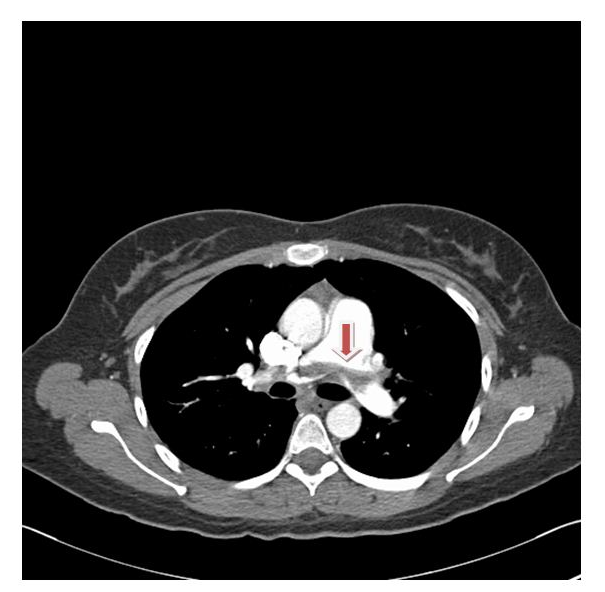

A 23 year old woman previously well presented with a sudden onset severe chest pain and shortness of breath. She was on oral contraceptive pills and has a family history of Protein C deficiency. Her father had recurrent pulmonary embolism from the age of 32 and her grandmother had a history of recurrent strokes from the age of 30. On examination, she was tachycardic, tachypneic and hypoxic. Her CXR was normal (Figure 1). However her CT pulmonary angiograghy showed a saddle pulmonary embolus (Figure 2). She was anticoagulated and booked for an echocardiogram.

Figure 2 CTPA showing pulmonary embolus.